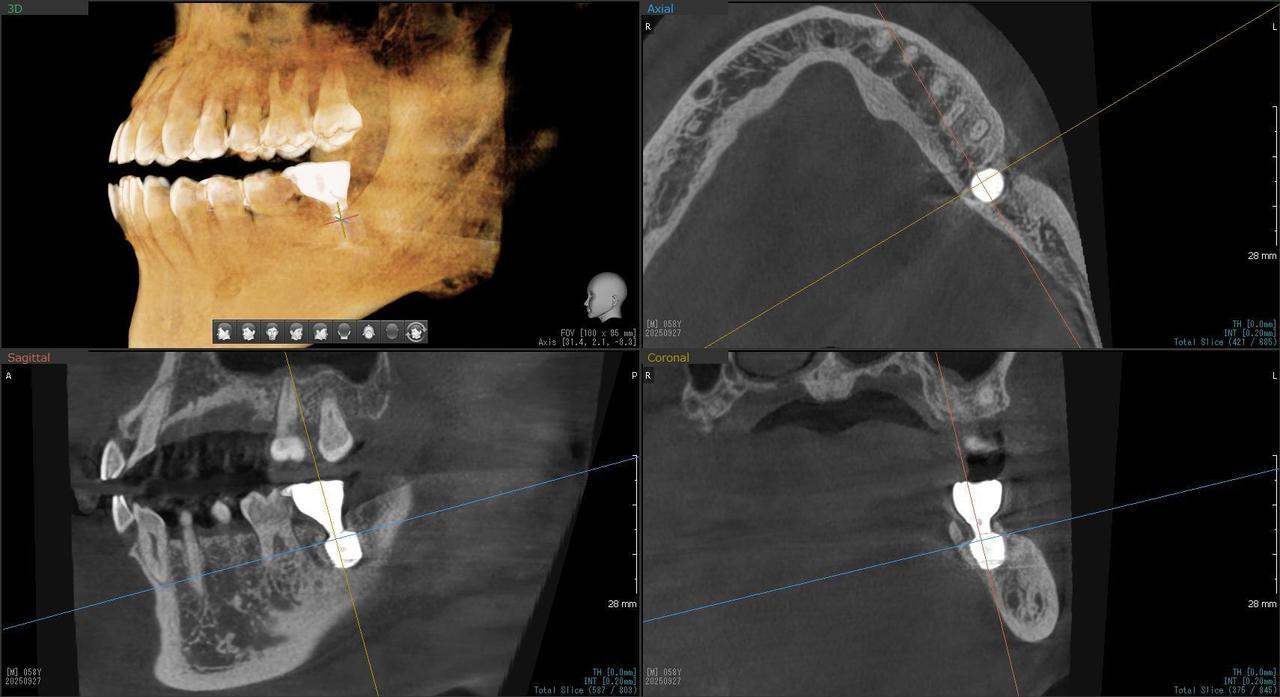

5.左上4番のインプラント抜歯即時埋入、左上6番の上顎既存骨1から2mmのグラフトレスサイナスリフト、左下56の大幅な骨欠損により、下顎神経の損傷を回避するために、ショートインプラントを使用し、左下56にインプラントを埋入し、最終補綴物は、左上456の3ユニットのジルコニアブリッジし、左下56は、ジルコニアの連結冠を装着したケース

Before

枚方市のインプラントの症例

After

M・I 様 女性 70代

症状としては、左下56は、歯周病で欠損したと考えられるが、かなりの骨欠損をともなっていた。左上456に関しては、動揺が大きく、炎症が起き、排膿、および、歯性上顎洞炎を起こしていた。

治療法としては、動揺がひどくなってきて、炎症の症状もあったため、左上56の抜歯を希望。インプラント治療をその後、希望したため、左上4に関しては抜歯即時埋入。左上6に関しては、既存骨1から2mmでインプラント治療が厳しい状態であったが、グラフトレスサイナスリフトを行い、治療期間5か月はかかるということを説明して、インプラント埋入をおこないました。その後、2か月半後、大幅に骨が欠損している下顎56に対して、ショートインプラントを使用して、下顎神経の損傷を避けて、インプラント埋入を終えています。その後2か月後に光学印象で印象を行い、上顎刺億456歯、3ユニットのジルコニアブリッジを装着。下顎左側56に関しては、骨欠損が大きいため、歯冠長がだいぶ長くなるため、ジルコニアの連結冠を装着して治療を終えた。

治療結果は、上顎6に関しては、既存骨が少なく、厳しい治療ではありましたが、5か月で治療を終え、患者様の負担を最小限に抑えるができたと考えます。(従来のサイナスリフトでは、このようなケースでは1年以上、1年程度の治療期間がかかるか、治療が不可能と言われるケースだと考えます。)また、下顎は骨欠損が大きく、下歯槽管のリスクが起きることが考えられますが、ショートインプラントを使用することで安全に治療を行うことができました。

治療の期間・回数:治療期間5か月(上顎456 3ピースブリッジの治療は5か月(上顎既存骨が2mm程度しかなく、骨結合に時間がかかるケースであったために、5か月の治療期間が必要であった。)(左下56に関しては2か月半で治療を終えています。)治療回数は、13回。

治療の価格:1,474,000円(税込)

治療費の内訳:左上46および左下56のインプラント基本料(フィックスチャー及び手術費用、投薬費用、レントゲン費用、インプラント上部費用(アバットメントおよびジルコニアクラウンの費用用)330000円(税込み)×4本分 1320000円(税込)。左上5ジルコニアポンテック費用88000円(税込)。オプション費用、左上4抜歯即時埋入加算(人工骨費用を含む)+グラフトレスサイナスリフト費用 33000円(税込)、左上6グラフトレスサイナスリフト費用 33000円(税込)

治療のリスクや副作用:手術後に、痛みや腫れ、出血、合併症などを引き起こす可能性があります。噛む感覚がご自身の歯と異なる場合があります。見た目がご自身の歯と異なる場合があります。手術後にメインテナンスを継続しないと、インプラントが抜け落ちる可能性があります。